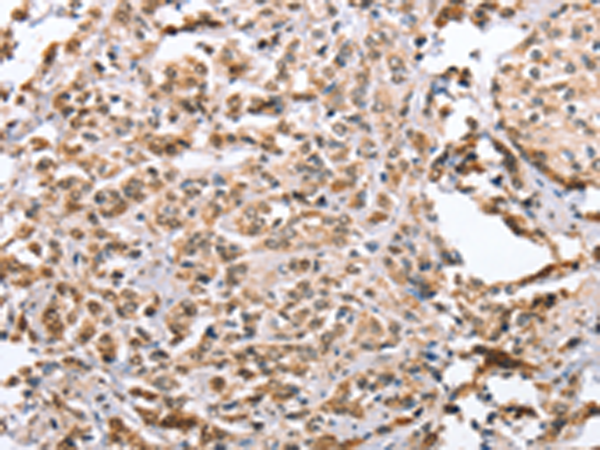

分类: 科研抗体货号: P03691别名: PPP1R69应用: IHC反应种属: Human